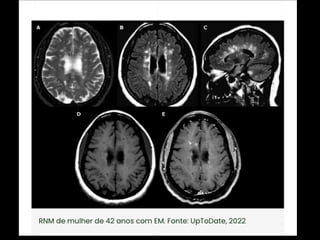

Diagnóstico:   Observação: ARM pode evidenciar áreas com pontos brilhantes indefinidos em indivíduos saudáveis; Gadolínio: • realçar lesões, • destacar se a doença está em estado ativo

critérios  McDonald  (2017)   • disseminação  no  espaço   – RM  por  ≥  1  lesões  hiperintensas  em  T2,   sintomá+cas  ou  assintomá+cas,  que  são   caracterís+cos  de  EM,  em  dois  ou  mais  das   seguintes  quatro  áreas  do  sistema  nervoso   central:     • periventricular,     • cor+cal/justacor+cal,  infratentorial  e  medula  espinhal.

• disseminação  no  tempo   – presença  simultânea  de  lesões  captantes  de   gadolíneo  e  lesões  não  captantes  em  qualquer   exame  de  RM,     – ou  nova  lesão  hiperintensa  em  T2  ou  captante  de   gadolínio  quanto  comparada  a  um  exame  de  RM   prévio,  independentemente  do  momento  em  que   foi  realizado.